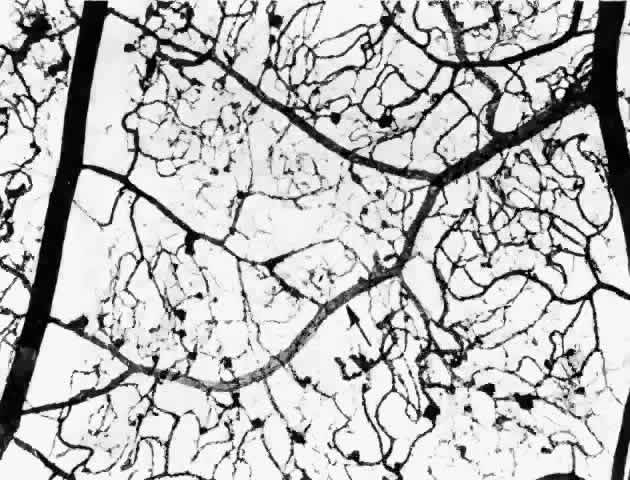

The retinal veins can also become irregular and tortuous with sausage-shaped dilatations. The vascular walls become diffusely permeable so that they both leak and stain with fluorescein. These changes also seem to be associated with ischemia. As shown by trypsin digestion, the beaded areas are hypercellular (Fig. 10).43 Diabetes is also a risk factor for branch retinal vein occlusion47 and central vein occlusion.43

Fig. 10. A and B. Sausage-shaped venules (arrows) result from irregularities in the venular walls. Note the arteriolar-venular connections and thickened capillary basement membranes (dark-colored capillaries). Retinal capillary microaneurysms tend to arise from cellular (viable) capillaries and cluster around acellular (nonviable) capillaries. The venular walls not only are irregular, but they also have an unusual presence of saccular microaneurysms (Inset 1, and Inset 3 from the area of the double arrows). Inset 2. Fundus appearance of microaneurysms, a cotton-wool spot, irregular venules, and intraretinal neovascularization in the form of a rete mirabile. (a = arteriole; v = venule) (A and B, PAS, × 16; Inset 1, PAS, × 40; Inset 2, fundus; Inset 3, PAS × 54)